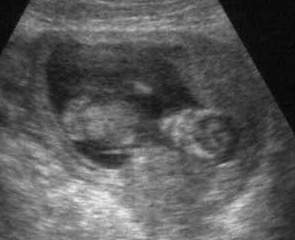

متعي ناظريك برؤيته في الاسبوع العشرين